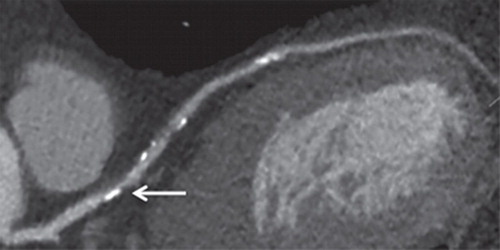

Ateroesclerosis coronaria subclínica y riesgo de infarto de miocardio

28 marzo 2023

En este estudio de cohortes realizado en Dinamarca, en personas asintomáticas, la detección de aterosclerosis coronaria obstructiva subclínica por medio de angiografía coronaria con TC se asoció con un riesgo más de 8 veces mayor de infarto de miocardio. Annals of Internal Medicine, 28 de marzo de 2023.